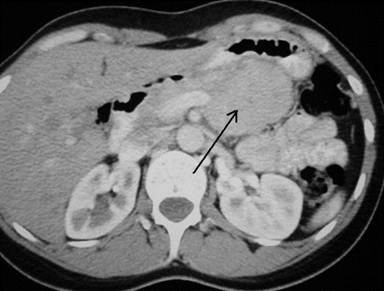

A 38-year-old woman with no previous surgical history presented with epigastric abdominal pain. Ultrasound examination and a computed tomography (CT) scan showed a 4 cm heterogeneous lesion in the pancreatic body. This tumor invaded the splenic artery and vein (Figure 1). No lymph node extension was noted. Endoscopic ultrasound-guided (Figure 2) fine-needle biopsy confirmed a neuroendocrine tumor. Biologic tests regarding the suspicion of a functional neuroendocrine tumor were normal. The patient was referred for surgical treatment.

Figure 1. Pancreatic tumor in the midportion of the pancreas on contrast-enhanced CT. |